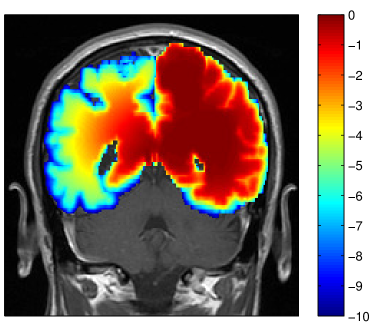

Refer to caption

Figure 3: Simulated tumor cell density based on the segmentation in figure 2 for parameters λw=4.2subscript𝜆𝑤4.2\lambda_{w}=4.2 mm and Dw/Dg=100subscript𝐷𝑤subscript𝐷𝑔100D_{w}/D_{g}=100 (a) and Dw/Dg=10subscript𝐷𝑤subscript𝐷𝑔10D_{w}/D_{g}=10 (b) . The color scale refers to the log10𝑙𝑜subscript𝑔10log_{10} cell density normalized to the carrying capacity.

In the manual delineation of the CTV used in the clinical plan, it is incorporated that the falx represents an anatomical barrier for the migration of tumor cells. Hence, the isotropic target expansion was trimmed manually. In the tumor growth model, the falx is modeled via a layer of CSF and is automatically accounted for through the assumption that tumor cells only migrate within white and gray matter. However, the corpus callosum connects the two hemispheres of the brain. The tumor growth model describes the migration of tumor cells through the corpus callosum (see figure 3 and 5a). As a consequence, the target volume based on the growth model is extended into the contralateral hemisphere. Figure 5a shows the tumor cell density overlaid on the coronal T1 gadolinium image. This illustrates the three-dimensional modeling of tumor spread via the model, including areas superior to the corpus callosum. This is not consistently accounted for in the manual CTV. In the manually drawn target volumes, the target is slightly extended into the contralateral hemisphere on the slices that show the corpus callosum, but not on the slices located superiorly and inferiorly (figure 5b). In the model derived target volumes, the target is extended further into the contralateral hemisphere, and the spread of tumor cells in superior-inferior direction beyond the corpus callosum is modeled.

Figure 5: (a) Log tumor cell density overlayed on the coronal T1 image showing spread of the tumor in the contralateral hemisphere (λw=4.2subscript𝜆𝑤4.2\lambda_{w}=4.2 mm and Dw/Dg=100subscript𝐷𝑤subscript𝐷𝑔100D_{w}/D_{g}=100). (b) Comparison of manual CTV (green) and model based CTV (red) (same contours as in figure 4.

In addition to the segmentation, the ratio of white and gray matter diffusion coefficient Dw/Dgsubscript𝐷𝑤subscript𝐷𝑔D_{w}/D_{g} influences the shape of the isolines of the tumor cell density. For Dg=0subscript𝐷𝑔0D_{g}=0, gray matter represents a hard boundary and tumor cells only spread in white matter. For Dw/Dg=1subscript𝐷𝑤subscript𝐷𝑔1D_{w}/D_{g}=1, tumor cells spread equally in white and gray matter and the shape of the target is solely influenced by anatomical constraints. In figure 3 the simulated tumor cell density is compared for Dw/Dg=10subscript𝐷𝑤subscript𝐷𝑔10D_{w}/D_{g}=10 and Dw/Dg=100subscript𝐷𝑤subscript𝐷𝑔100D_{w}/D_{g}=100. For smaller Dw/Dgsubscript𝐷𝑤subscript𝐷𝑔D_{w}/D_{g}, the cell density is more washed out (figure 3b) compared to a larger Dw/Dgsubscript𝐷𝑤subscript𝐷𝑔D_{w}/D_{g} where the tumor cell density follows more closely the white matter structure (figure 3a). It has been discussed above that the cortical gray matter has a thickness of only a few millimeters. As a consequence, varying Dw/Dgsubscript𝐷𝑤subscript𝐷𝑔D_{w}/D_{g} has little impact on the global shape of the target volume. The most significant changes for this patient are around the lateral sulcus.